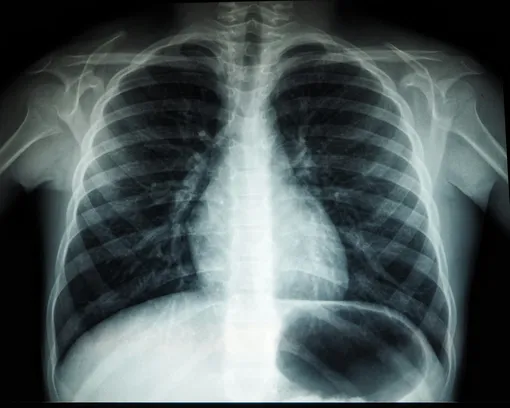

Туберкулез — инфекционное заболевание, которое можно предотвратить и вылечить. Его вызывают бактерии (палочка Коха), которые чаще всего поражают легкие. Он распространяется воздушно-капельным путем при кашле, чихании и сплевывании мокроты. К основным опасностям туберкулеза относятся следующие факторы:

- Болезнь чаще всего поражает легкие, но может затрагивать и другие органы: кости, мозг, почки, кожу, лимфатическую и нервную системы.